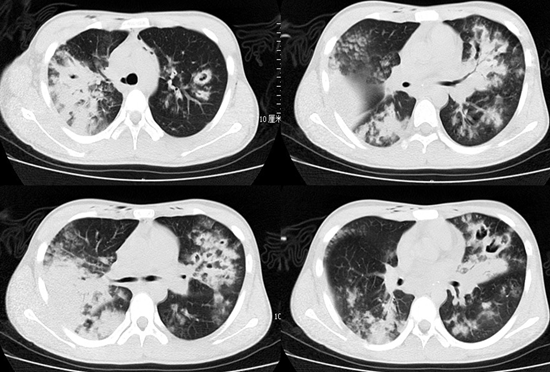

病例分析

以下是2例中年男性患者,急性病程,有高血压和冠心病病史,入院时均存在低淋巴细胞血症,并且CD4+T细胞计数偏低,影像学相对比较典型,都是弥漫磨玻璃影合并实变,第2例患者实变范围更广。第1例患者入院后第4天BALF涂片提示了丝状真菌,因此高度怀疑曲霉菌感染,抢先抗真菌治疗,第2例患者始终无确切的真菌感染证据,因为患者淋巴细胞低,经过抗病毒和抗细菌治疗后病情仍然进展,于第4天给予了预防性抗真菌治疗。实际上两例患者抗真菌治疗的时间相差不多,距出现症状的时间也相近。最终这两例患者都因病情恶化而死亡。

图片